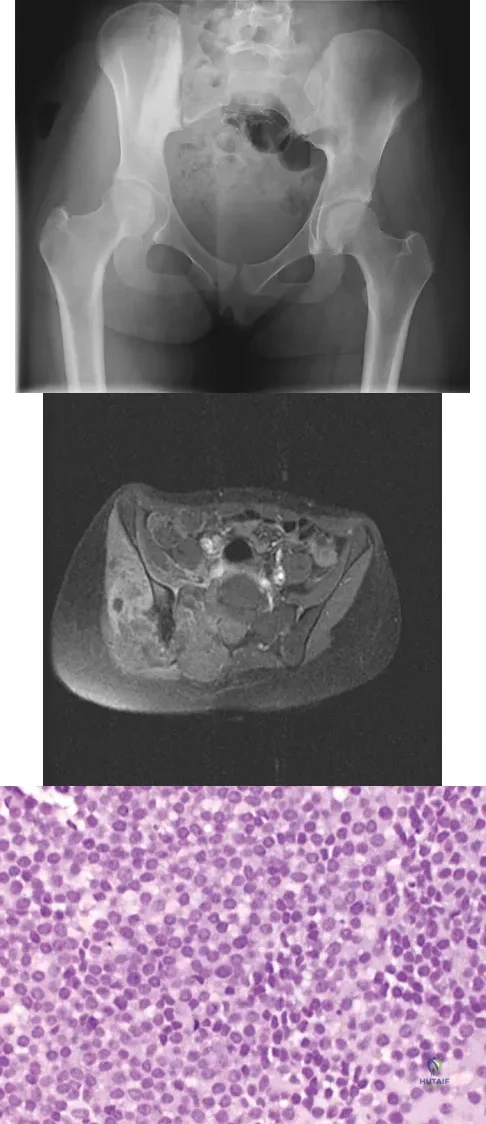

A 16-year-old girl has had hip pain for 1 year. Approximately 2 months ago she noted the development of a hard mass in the right buttock that has steadily increased in size. She now reports severe pain in the right buttock, with radiation down the leg and numbness involving the right foot and toes. A radiograph is shown in Figure 70a and an axial postcontrast T1-weighted MRI scan is shown in Figure 70b. A biopsy specimen is shown in Figure 70c. The chest CT shows multiple lung metastases. Treatment of this lesion should consist of

Explanation